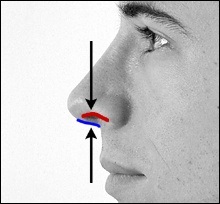

Mielőtt nagyobb acanthion. Ez az, amit úgy néz ki, a művelet során. Az ábrán a jobb ez sárga színű. Acanthion columella található, közvetlenül alatta, ahol a felső ajak határos az alapja az orrát.

Része a gerinc, amelyeket el kell távolítani jelzi a kék vonalon. Removal végezzük vésővel.

Fent és lent a beteg bemutatja fényképeket készített műtét előtt és után. Kék vonal a jobb szélén az alsó fényképekkel kijelölt columella és piros - szélén a bal orrlyukon. Az orrlyukak nyitott része által határolt két fekete nyilak. Mint látható, a műtét után orrlyukak nyitottak része csökkent, így az orr sokkal vonzóbb megjelenésű.